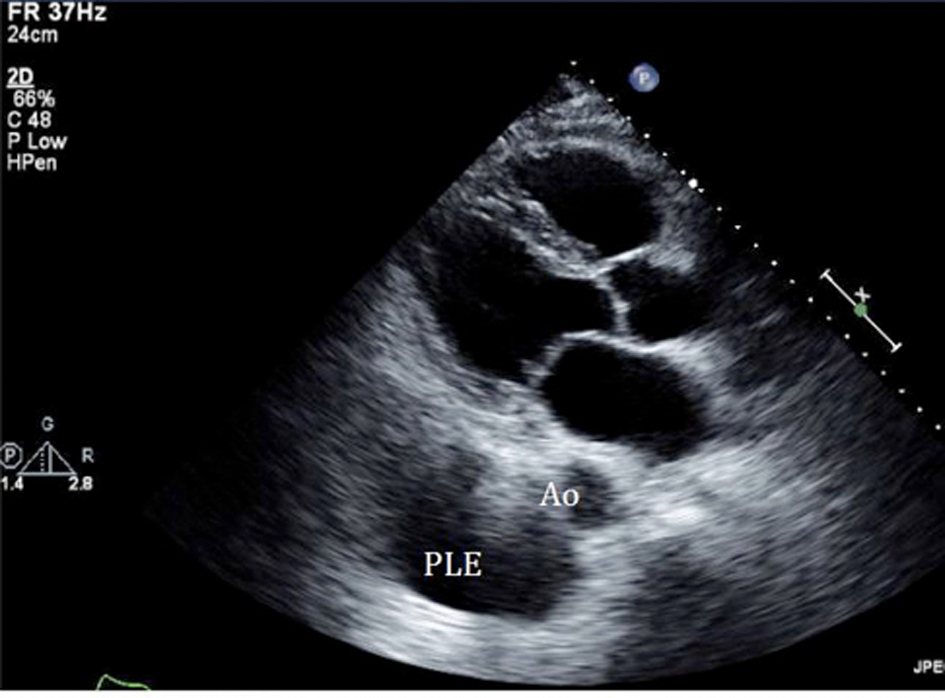

An initial complete blood count showed a mild anemia with hemoglobin of 11.2 g/dl. An anterior-posterior chest x-ray showed bilateral interstitial edema with pleural effusions. A transthoracic echocardiogram was performed and found a large pericardial effusion (Fig. 1) with tamponade physiology (Fig. 2). No intracardiac masses were noted. A right heart catheterization was also performed. The initial right atrial (RA) and intrapericardial pressures were elevated at 38 and 31 mmHg, respectively (Fig. 3). The patient underwent urgent pericardiocentesis after warfarin reversal with vitamin K and fresh frozen plasma. Approximately 1060 ml of blood-tinged fluid were removed. After pericardiocentesis there was no residual pericardial fluid assessed by transthoracic echocardiogram (Fig. 4), despite that the RA pressure remained significantly elevated at 33 mmHg. The RA tracing revealed a prominent Y descent (Fig. 5). Due to the patient’s supratherapeutic INR (international normalized ratio) and transient neurologic deterioration from sedation, simultaneous right and left heart catheterizations were not performed. The hemodynamics were compatible with effusive-constrictive pericarditis. Cytology and flow cytometry in the pericardial fluid revealed the presence of monoclonal kappa B-cells, CD 5 negative, CD 10, CD 19, CD 20, and CD 45 positive. Morphologically, the cells were consistent with large B-cell non-Hodgkin's lymphoma. A bone marrow biopsy ruled out systemic lymphomatous involvement. Positron emission tomography (PET) scan confirmed the diagnosis of primary cardiac lymphoma (PCL) showing thickening of the anterior pericardium with an standardized uptake value (SUV) of 5.0. There was no malignant uptake in any other structure such as lymph nodes, other serosal surfaces, or solid organs.

![]() Click for large image | Figure 4. Echocardiogram performed after the pericardiocentesis showed resolution of the effusion, instead pleural effusion (PLE) becomes more evident as an echolucent space below the aorta (Ao). |

Effusive-constrictive pericarditis is a rare form of pericardial disease that is usually diagnosed after pericardiocentesis. The hallmark is the persistence of an elevated right atrial pressure after drainage of pericardial fluid, traditionally documented by normalization of intrapericardial pressure. In our case we documented by echocardiogram with minimal residual pericardial fluid. Other classic features include reversed X/Y ratio in the atrial pressure tracing after drainage of the pericardial fluid, dip-plateau morphology in the ventricular tracings and accentuation of the interventricular interdependence. Its diagnosis is important as patients might require pericardiectomy for treatment of right sided heart failure [7-10].